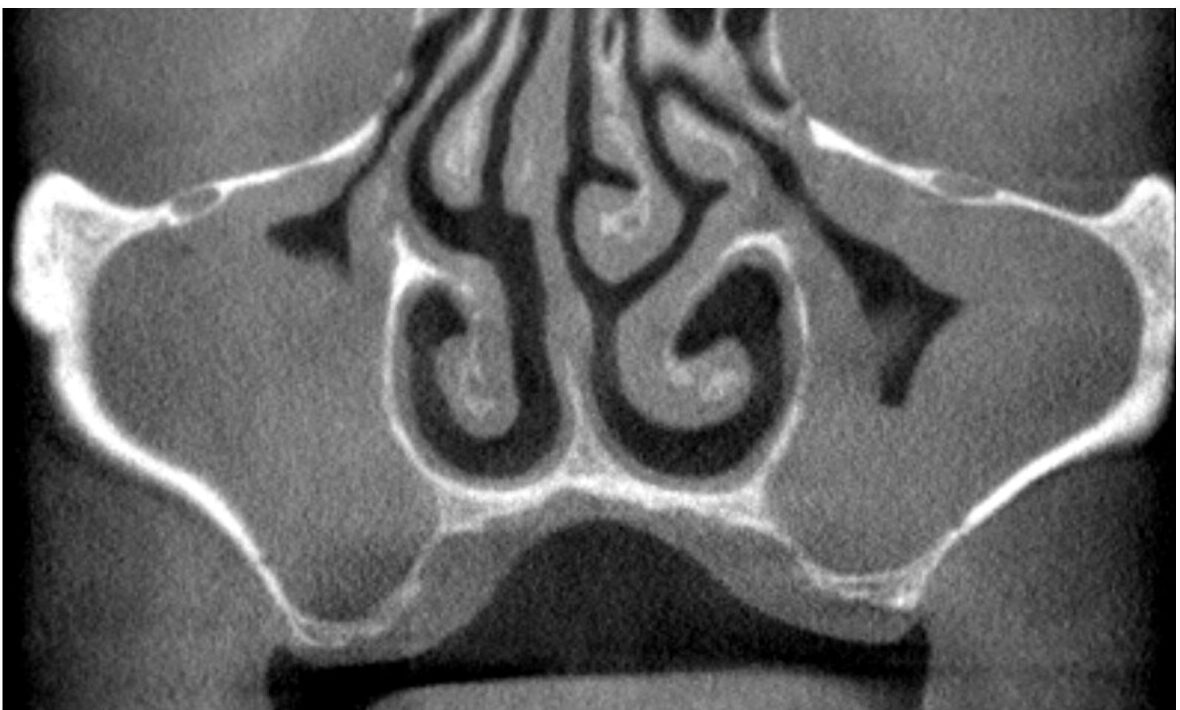

• ANATOMIA E FISIOLOGIA DELL’ATROFIA DEL MASCELLARE

• INDAGINI DIAGNOSTICHE RADIOGRAFICHE

• PIANIFICAZIONE E TECNICHE CHIRURGICHE DEL RIALZO DI SENO MASCELLARE (MINI E GRANDE)